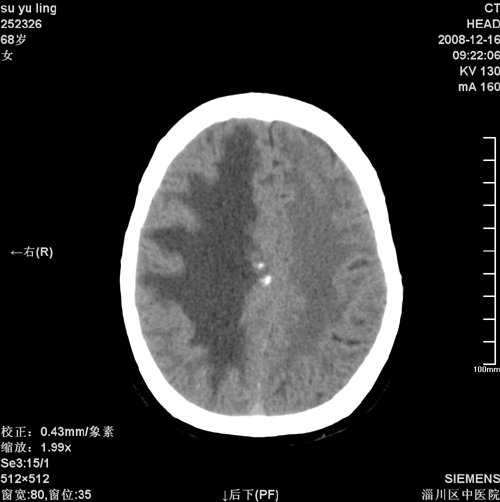

女,68岁,左侧肢体活动不利。

病灶比较均匀钙化,水肿明显,紧贴颅顶与大脑镰并跨越大脑镰----支持脑膜瘤

1)考虑镰旁脑膜瘤钙化。2)小脑萎缩。